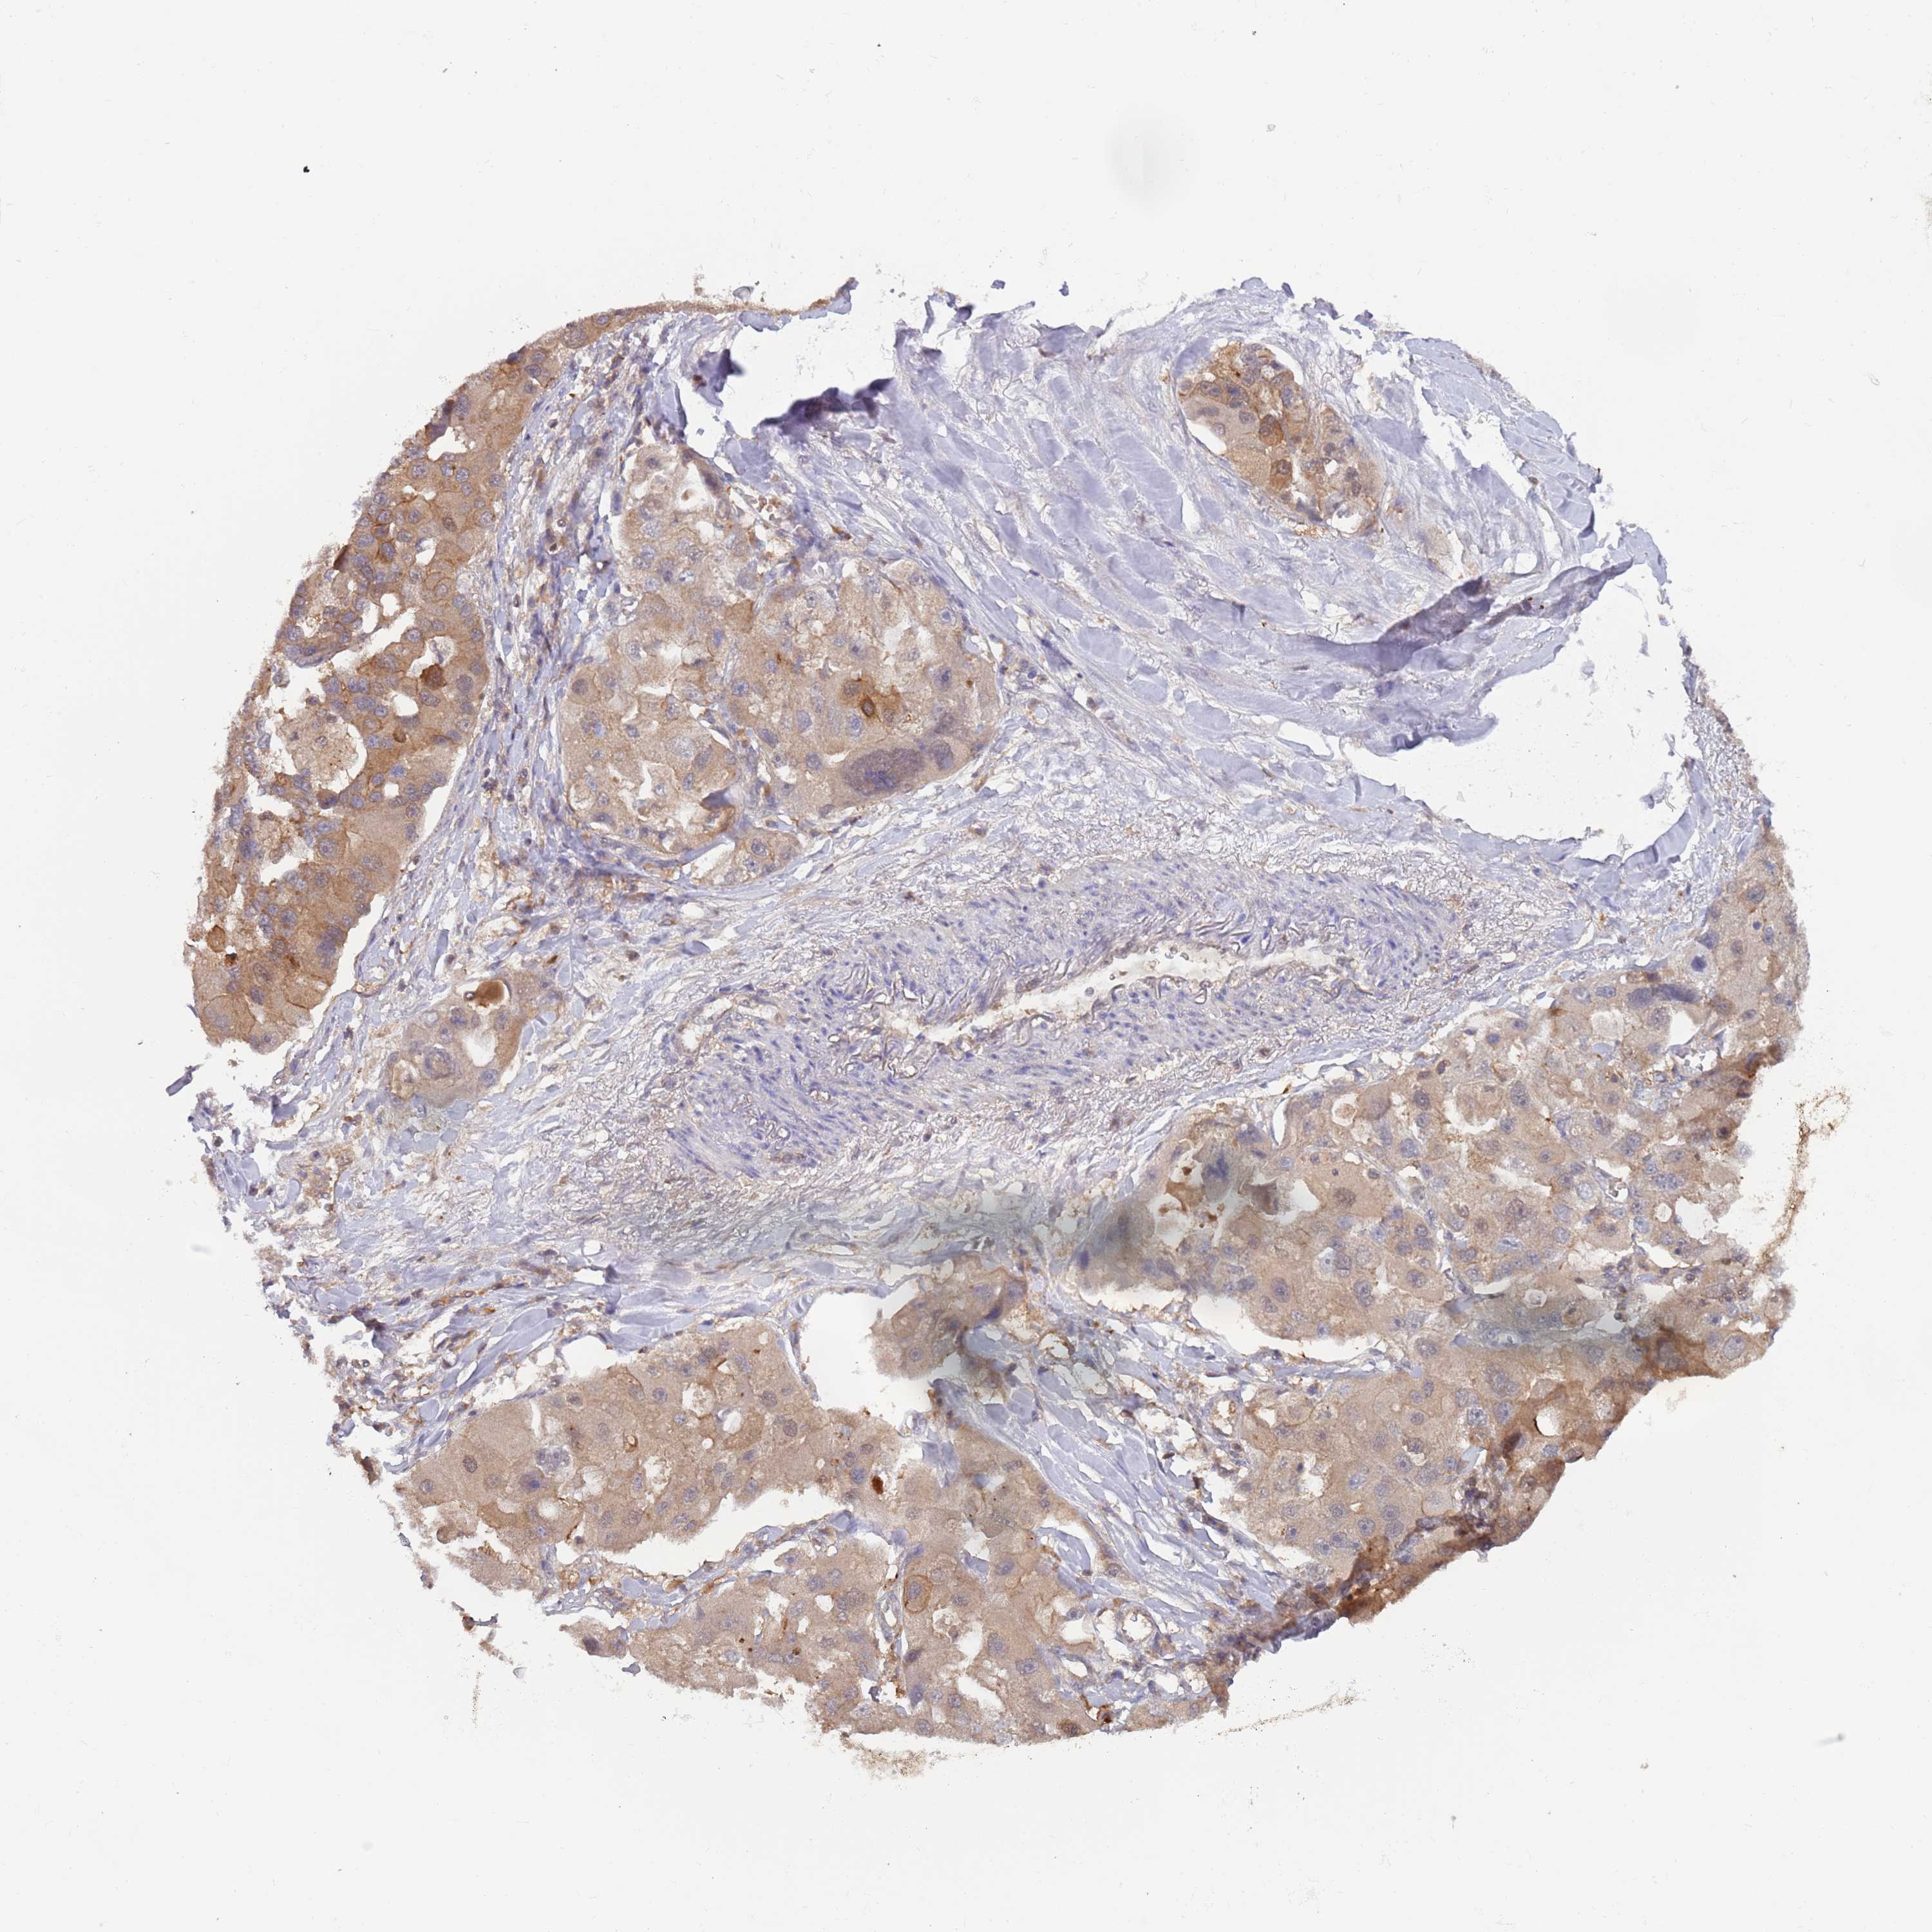

CANCER LUNG CANCER Show tissue menu

LUAD TCGA LUAD VALIDATION LUSC TCGA LUSC VALIDATION PROTEIN LUAD CPTAC PROTEIN LUSC CPTAC PROTEIN EXPRESSION

ANTIBODIES

AND

VALIDATION